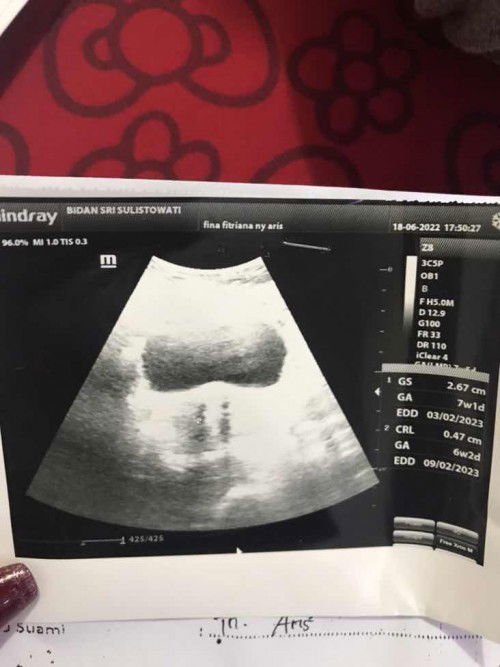

Hasil usg 7 minggu

Ko ga ada kantongnya apa normal? Klo yg diatas gede itu kantong kemih katanya,

Masih bingung sm hasil usg

Pas usg 7 minggu 5 hari, skrg udh 8 minggu 3 hari. Tpi itu masih kecil berupa kantong blm ada janinnya. Apakah normal? Sy tkt krna dokter bilang tkt ga berkembang🥺